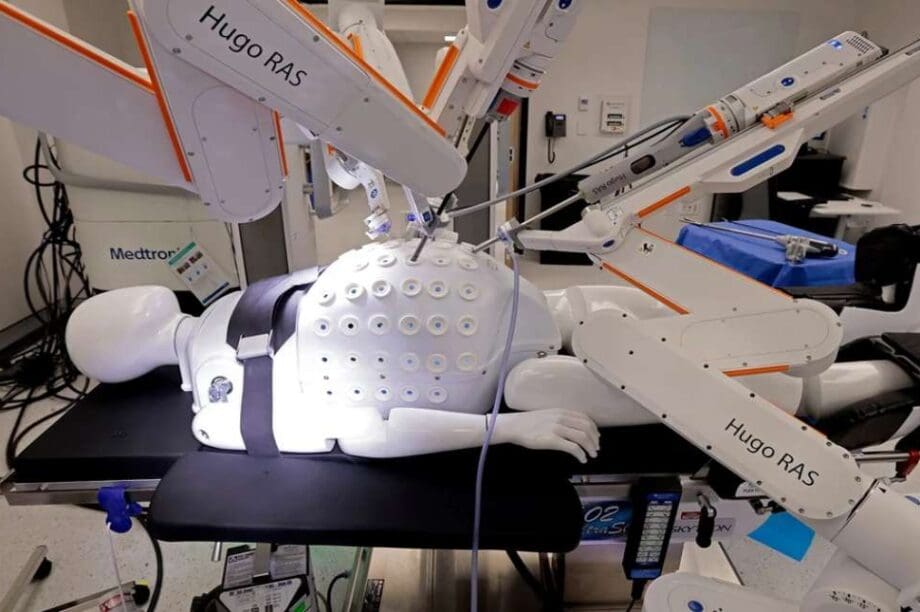

Το ρομπότ πέτυχε ποσοστό επιτυχίας 98,5% πολύ πάνω από τον αρχικό στόχο